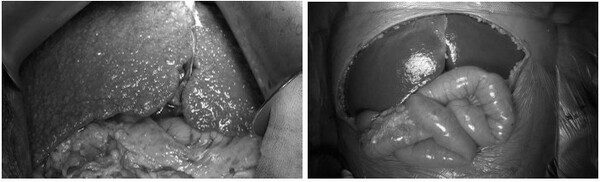

진행성가족성간내답즙정체증에 대해 고홍 교수는 "진행성이라는 말은 점점 나빠진다는 얘기이고, 가족성은 가족 내에 유전적 성향을 갖는다는 것"이라며 "'간 내'는 간 안에 계속 문제가 된다는 것으로 끊임없는 간 손상을 유발하는 것을 뜻하고, '담즙정체증'은 담즙이 내려가지 않고 간에 축적돼 결국 간이식으로 넘어갈 수밖에 없는 질병의 특징을 가지고 있다"며 생후 6개월 아기의 간이 이 병으로 간이식이 필요할 정도로 망가진 사례를 들었다(사진).

고 교수는 "이런 수술은 수술 리스크가 있고 여러 가지 문제가 있어서 수술이 완치법이 될 수 없다"며 "결국 이런저런 약을 쓰다가 안 되면 결국 간이식을 하게 된다. 간이식을 못하면 사망한다. 생후 6개월짜리 아기 간이 이 정도(사진)로 망가졌으니 간이식을 하지 않으면 생명을 유지할 수 없다"고 PFIC의 치료현실을 짚었다. 이런 까닭에 지난해 8월 국내 허가된 고가 PFIC 신약인 '오데빅시바트(제품명 빌베이)'의 빠른 급여가 절실한 상황이다.